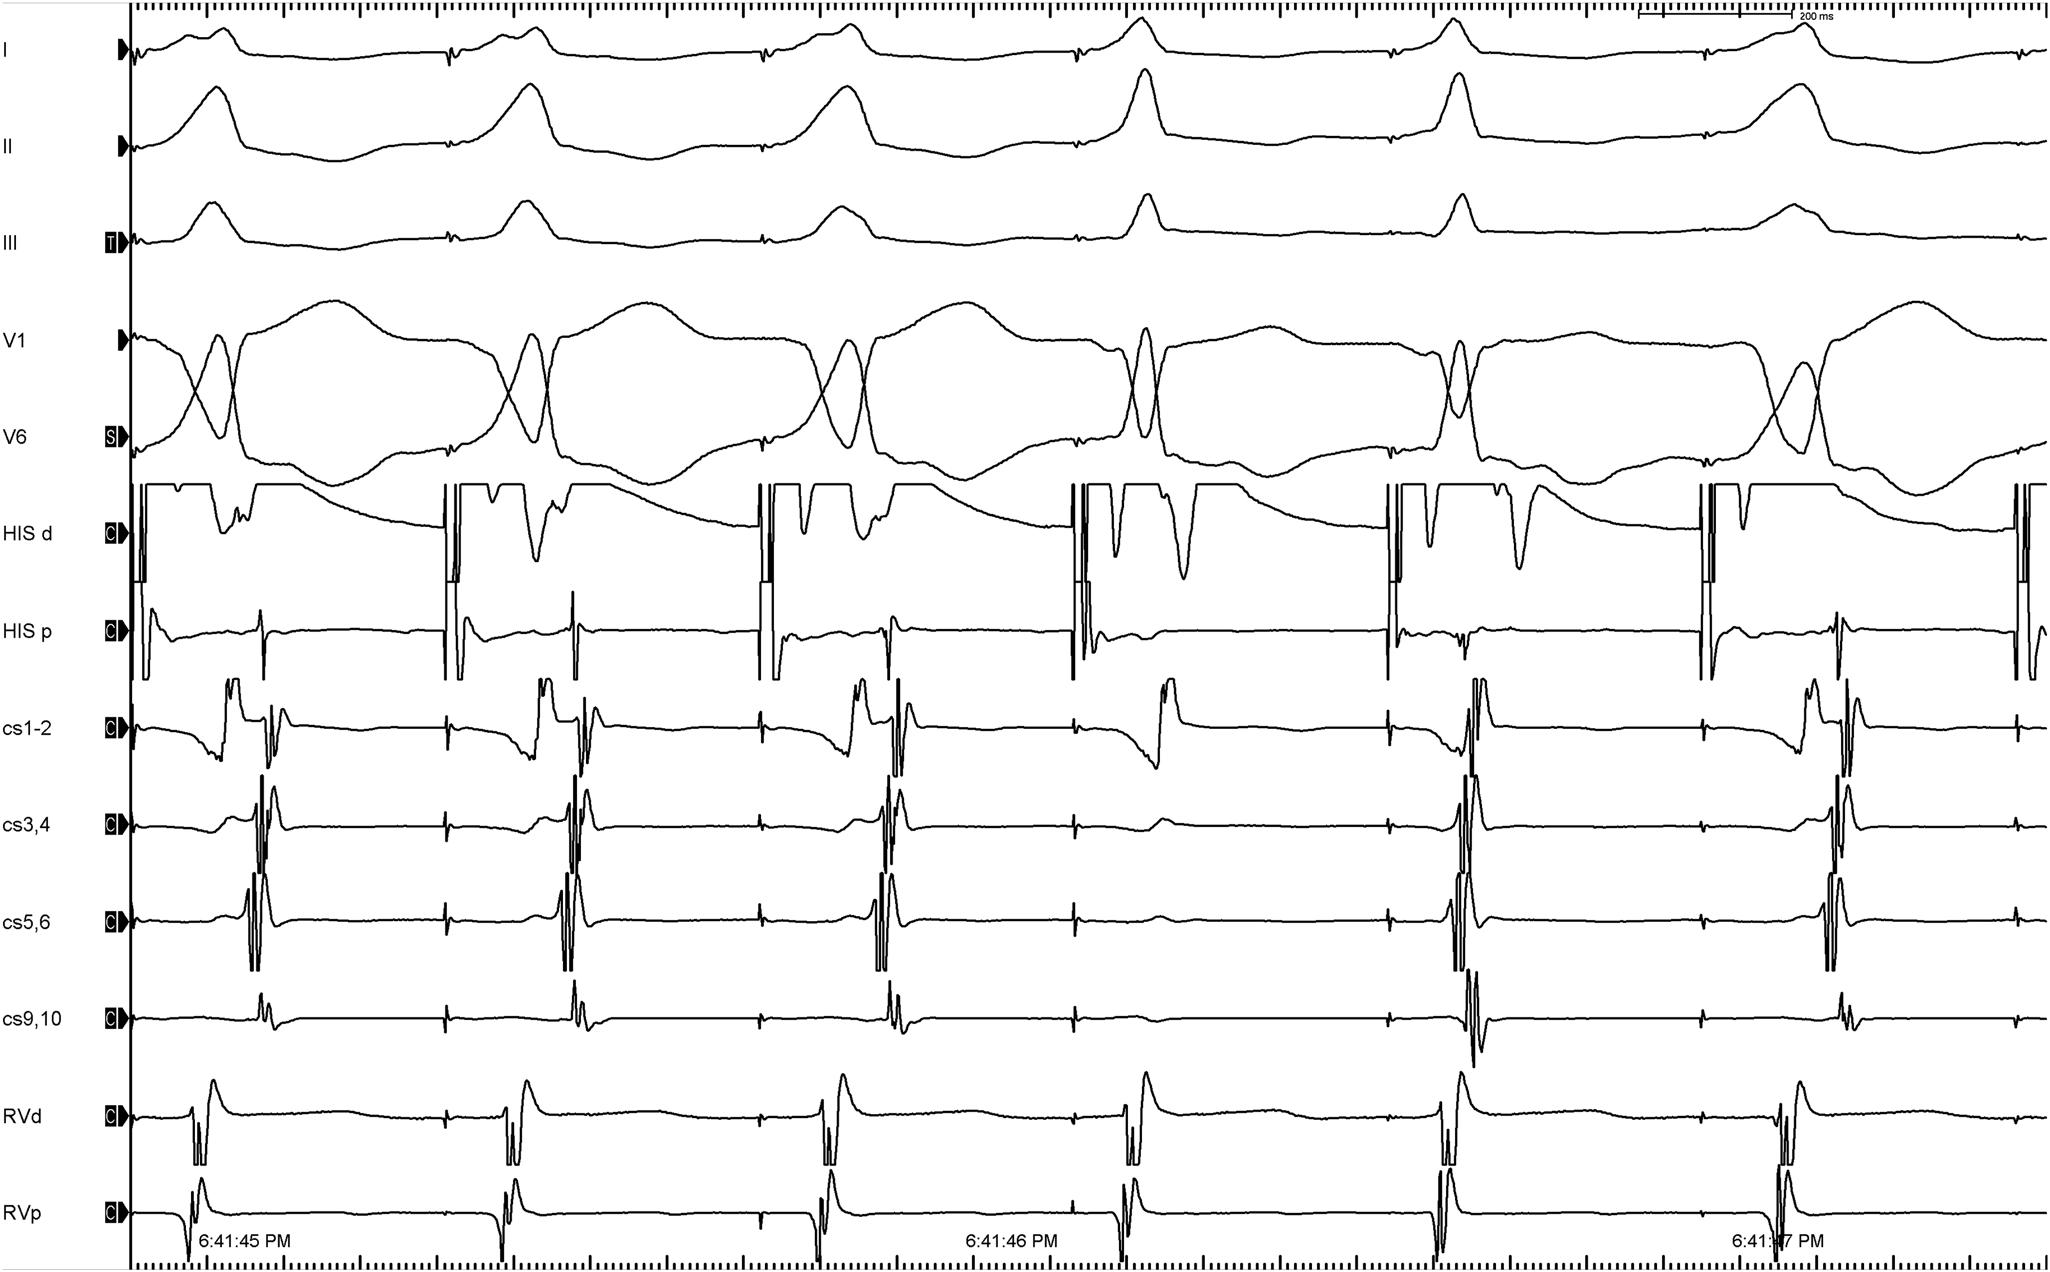

Intracardiac - Tachycardia

1b.jpg

• Normal HV, not VT

• No split His - Not intra His reentry

• Change in A activation due to fusion with sinus

SVT with V > A, central A activation.